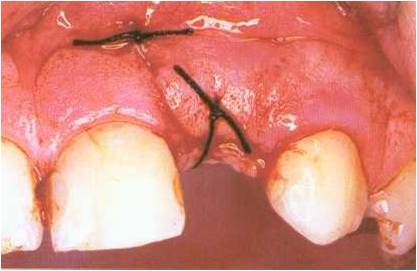

The first suture draws the flap into the mesial corner

of the defect, and the second closes the gaping anterior

relieving limb of the incision.